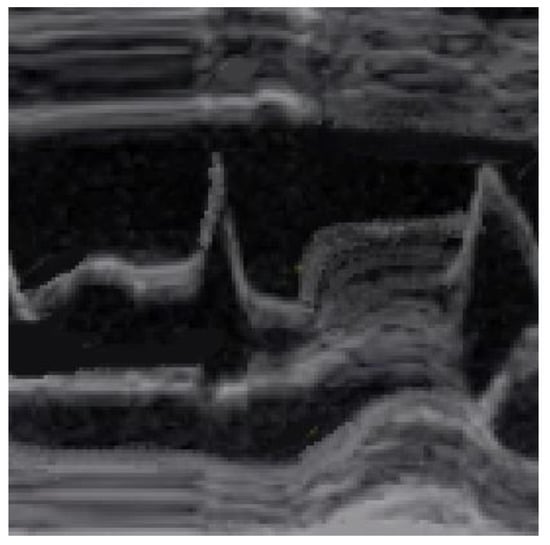

SAM and its severity are assessed via the M-mode from a short-axis view at the mitral valve level. SAM is defined as (1) incomplete if the mitral anterior and/or posterior leaflets do not touch the IVS, as (2) mild if mitral–septal contact occurs in the late systole and for less than 10% of the duration of the systole, and as (3) severe if it starts mid-systole and occupies more than 30% of its duration.

SAM is characterized by an abrupt anterior movement of the mitral valve during contraction, reaching its peak before the maximum movement of the posterior wall; this characteristic allows the differentiation of true SAM from SAM produced by an exaggerated anterior motion of the mitral valve, which reaches its peak after the full contraction of the posterior wall, i.e., “pseudo-SAM” [14] (Figure 3).

Figure 3. Pseudo SAM: the peak of SAM reaches after the full contraction of the posterior wall.